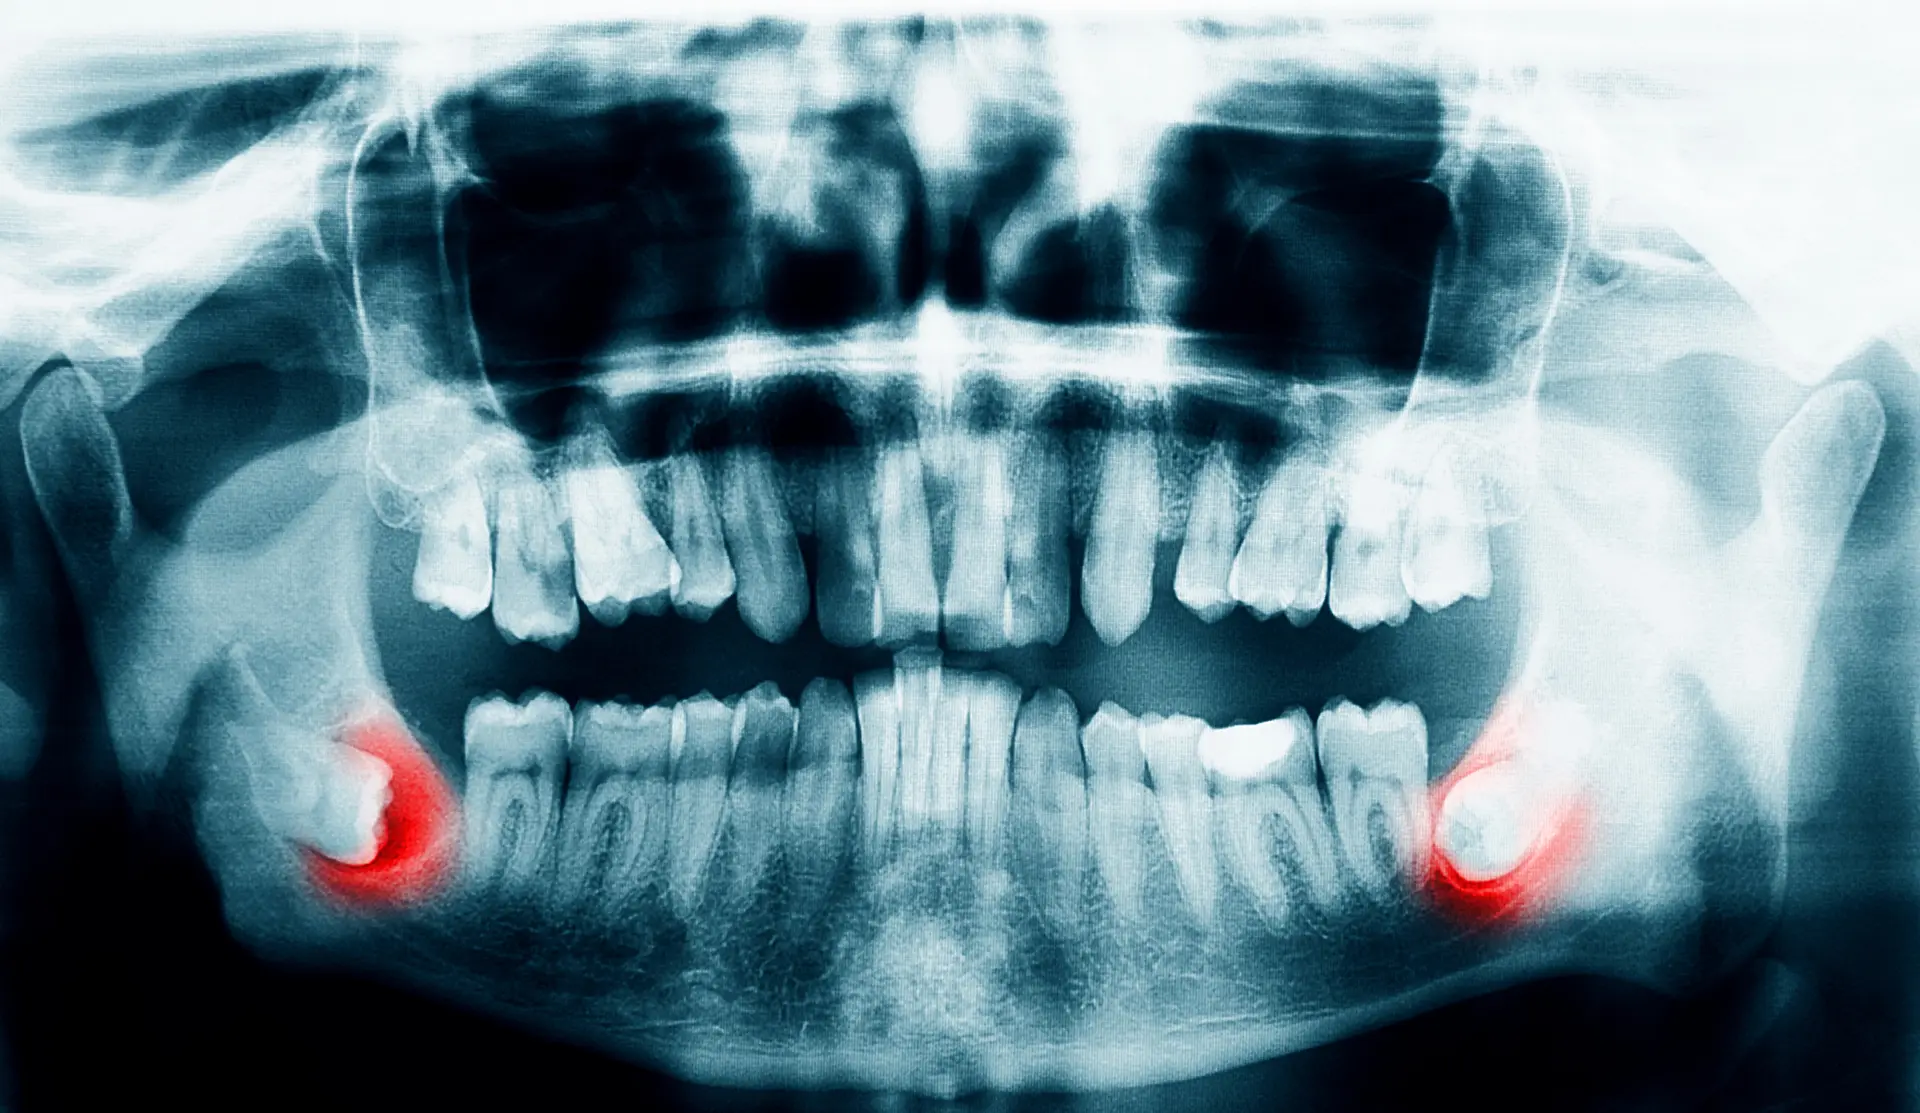

If your doctor tells you that you need your wisdom teeth removed, you may be scared but not surprised. We’ve all seen our friends, family, and loved ones go through it. Though common, removing your wisdom teeth can be a complicated procedure. That’s why it’s important to go to an expert who specializes in complex issues of the teeth and mouth. Oral surgeons are well-equipped in treating problematic wisdom teeth and preserving your oral health.

Wisdom teeth often have to be extracted to ensure the rest of your teeth stay healthy. Most wisdom teeth erupt misaligned, which can cause tooth crowding and disruption in your teeth and gums. This is not only painful but can make oral hygiene more difficult. Another common reason for wisdom teeth extraction is a partial eruption. This encourages bacteria to accumulate in the pockets of your gums, putting you at risk for gum disease, infection, and tooth decay. That being said, sometimes wisdom teeth don’t always need to be removed. If your wisdom teeth erupt properly aligned and don’t impact your other teeth, your doctor may not recommend extraction. But generally, wisdom teeth need to be removed to preserve a healthy smile.